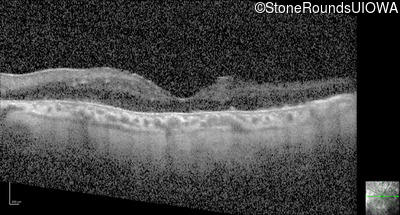

Optical Coherence Tomography - Right - 20/150

Exemplar / OCT Stack

OCT Stack